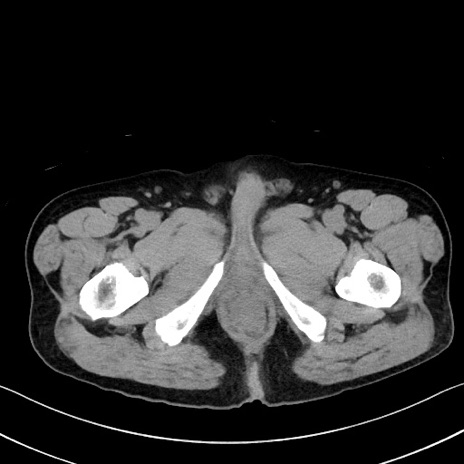

症例35(横断像)

【症例】70歳代 男性

【主訴】腹部膨満、嘔吐

【現病歴】昨日より腹部膨満感出現。本日増悪し、仙痛出現。嘔吐あり、受診。

【既往歴】糖尿病、胆摘後

【身体所見】BP 149/80mmHg、HR 74/min、BT 35.9℃、腹部:膨満、軟、圧痛なし。腸雑音減弱あり。上腹部正中切開瘢痕あり。

【データ】WBC 13500、CRP 1.72